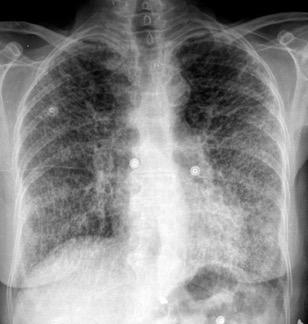

Marzo 2014: Perforación longitudinal distal secundaria a episodio de vómito (síndrome de Boerhaave). Derrame pleural izdo. que evoluciona a empiema.

Wang C-T et al. Tension hydropneumothorax in a Boerhaave syndrome patient: A case report . World J Emerg Med, 2021. Katabathina V et al. Nonvascular, nontraumatic mediastinal emergencies in adults:a comprehensive review of imaging findings. Radiographics. 2011.